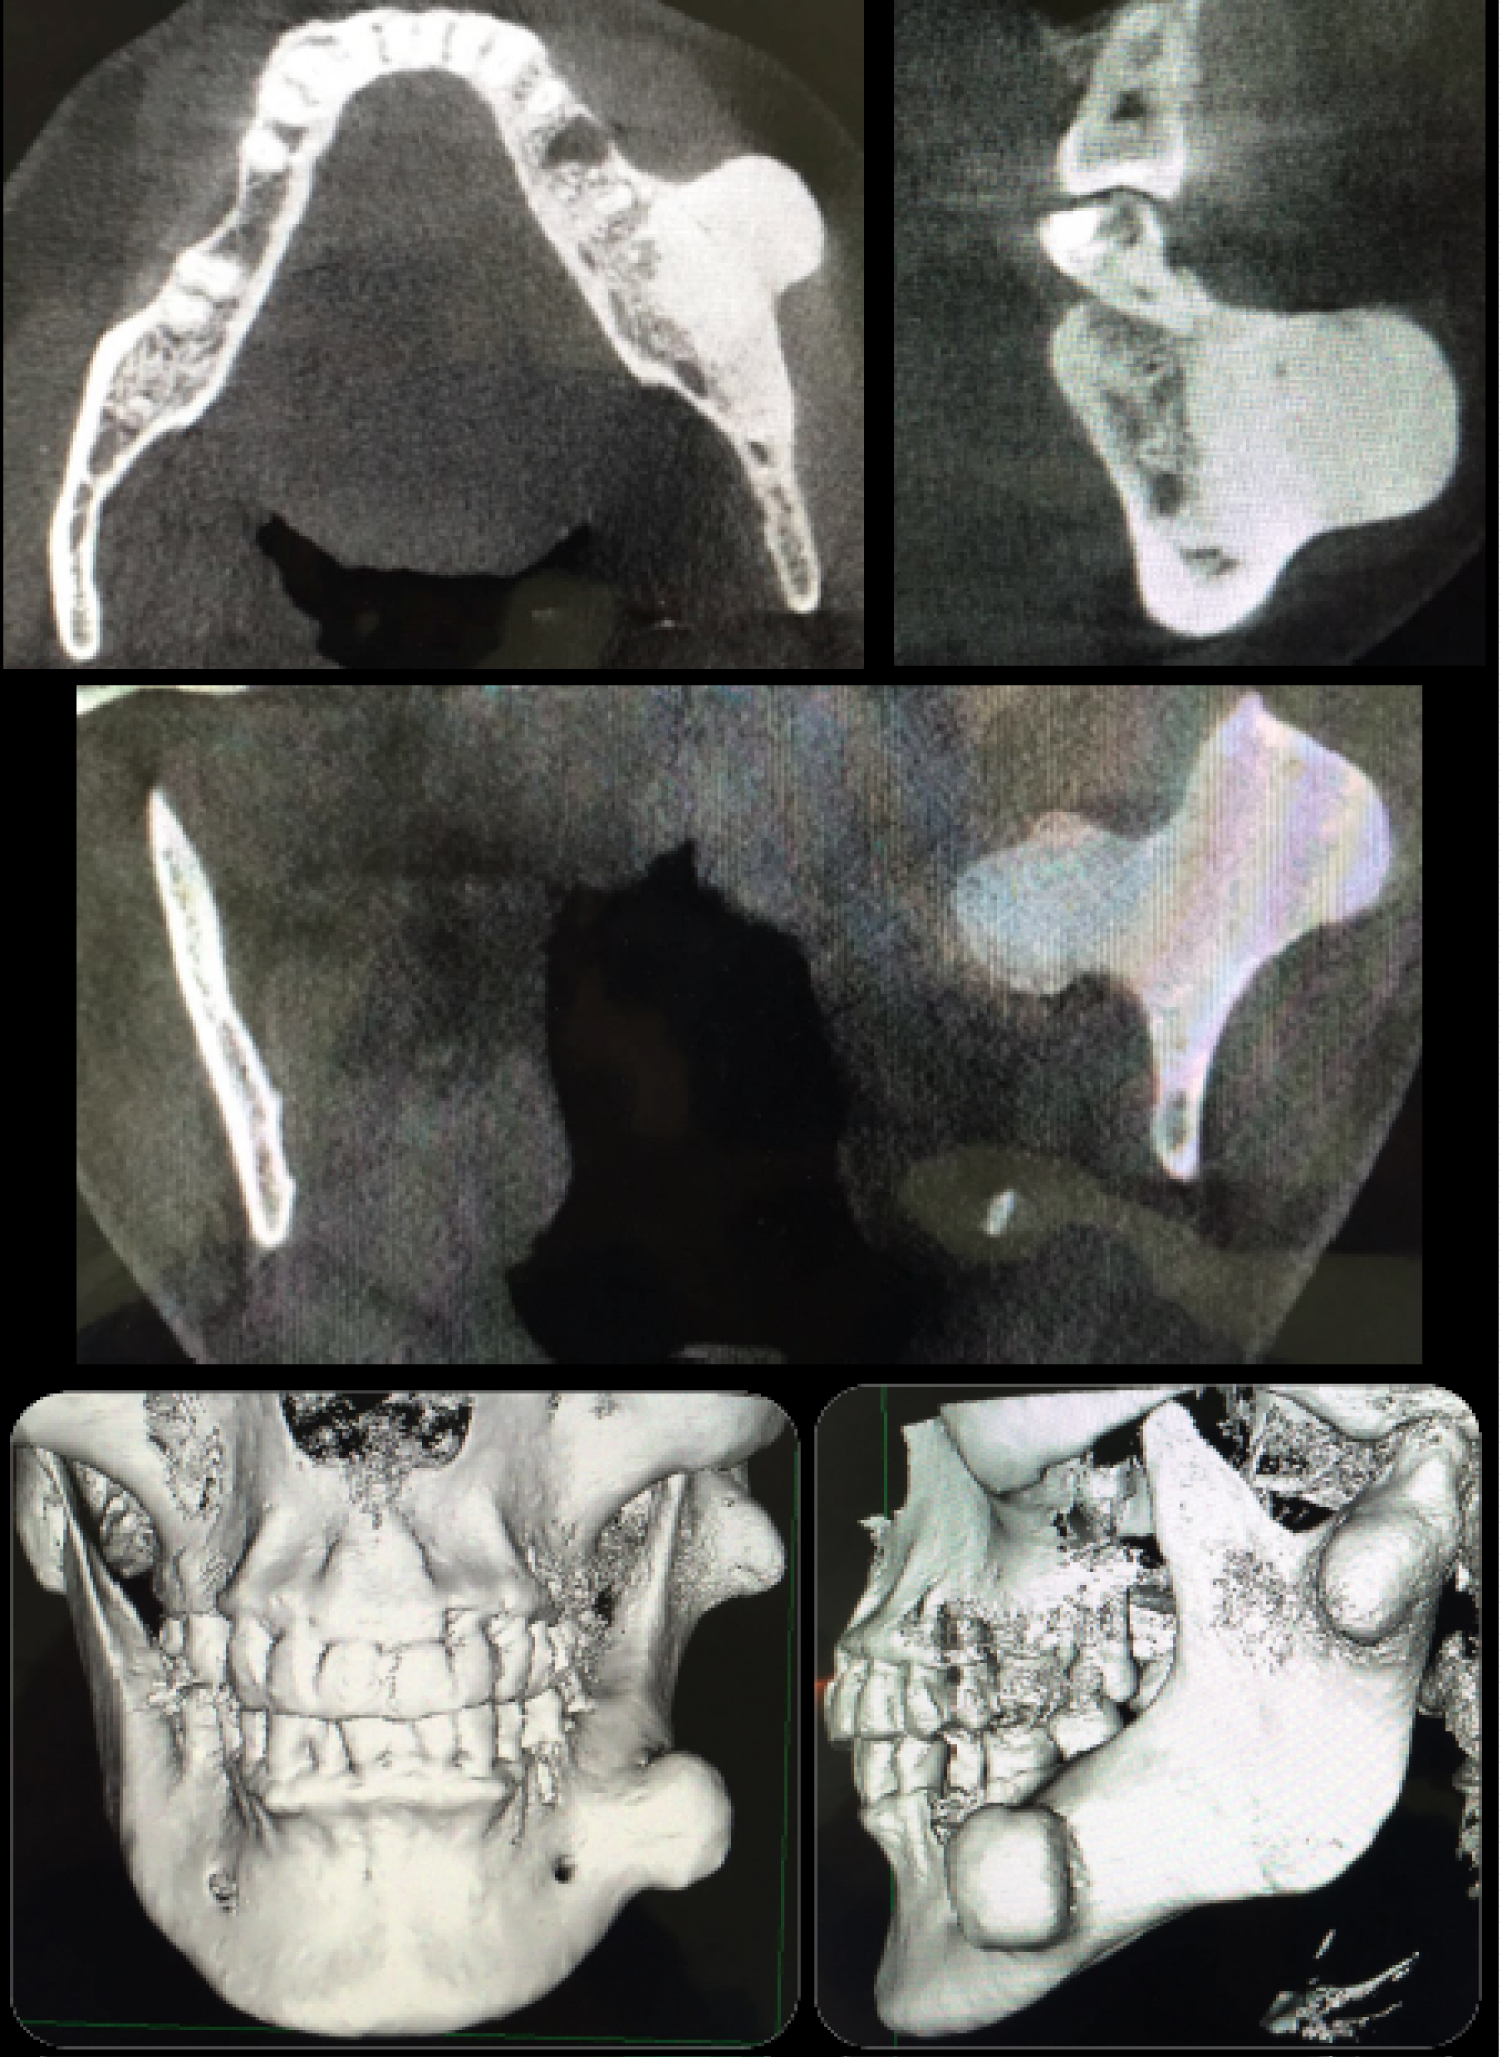

The delayed biopsy confirmed the diagnosis of compact peripheral osteomas, where a benign osteogenic lesion was observed through staining with hematoxylin and eosin, which contained large areas of highly compact lamellar bone deposition, proliferation of irregular trabeculae, with few osteons and spaces marrow, containing hematopoietic marrow tissue with cellular connective tissue, fibroblast-like spindle cells, and some blood vessels (Figure 4). The day after surgery, the patient was discharged, with the indication of periodic controls. One year after clinical and radiographic controls, an improvement in symptoms was observed, as well as a correction of facial asymmetry (Figure 5). In addition, a normal anatomy is observed in the control scanner, with no signs of recurrence (Figure 6).

Figure 6: Post-operative study. Axila and coronal sections of the CT, and three-dimensional computed tomography reconstruction (12 months post-operative). Front and lateral view, where a complete restoration of the normal mandibular anatomy is observed, without radiographic signs of recurrence. View Figure 6